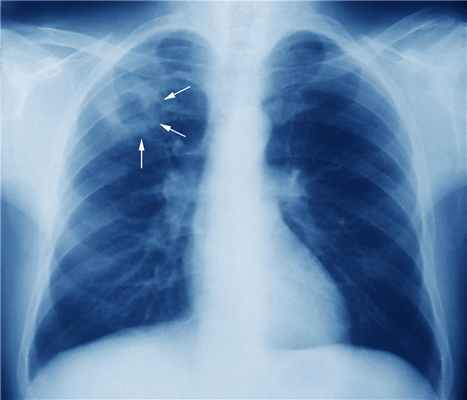

В настоящее время туберкулез бронхов чаще наблюдается у больных ВИЧ-инфекцией как осложнение туберкулеза внутригрудных лимфатических узлов [4]. У 10–20% иммунокомпетентных пациентов из-за неспецифических проявлений заболевания, постепенного начала, малосимптомного течения и отсутствия изменений при рентгенографии грудной клетки диагноз устанавливается поздно, при развитии осложнений. На рентгенограммах органов грудной клетки появляются участки поражения легочной ткани в виде бронхогенной диссеминации, участки гипо- и гипервентиляции, что вызывает определенные дифференциально-диагностические трудности. Осложнения в виде развития стенозов бронха у лиц старшего возраста нередко трактуются как опухоли бронха.

Рентгенография легких при изолированном туберкулезе бронхов, не осложненном бронхостенозом и бронхогенным обсеменением, не выявляет изменений.

При рентгенотомографии в отличие от гематогенно-диссеминированного туберкулеза легких двусторонний туберкулез субсегментарных бронхов характеризовался асимметричностью легочного поражения с большим участием нижних отделов легких и резким полиморфизмом изменений. Здесь наряду с очаговыми тенями средних и крупных размеров присутствовали и уплотненные стенки бронхов, и перибронхиальная их инфильтрация при полном отсутствии деструктивных изменений (рис. 9).

Отличить воспалительно-ателектатические изменения в легком от инфильтративного туберкулеза помогала рентгенологическая картина в виде объемного уменьшения легкого или его доли, однородный характер затемнения и отсутствие распада, от рака — данные бронхоскопии, свидетельствовавшие о тяжелом специфическом поражении бронхиальной стенки со стенозом просвета бронха, причем у многих с признаками как свежих, так и старых изменений в ней. Но в отдельных случаях только операционная биопсия позволила дифференцировать туберкулез от рака бронха (рис. 10, 11).